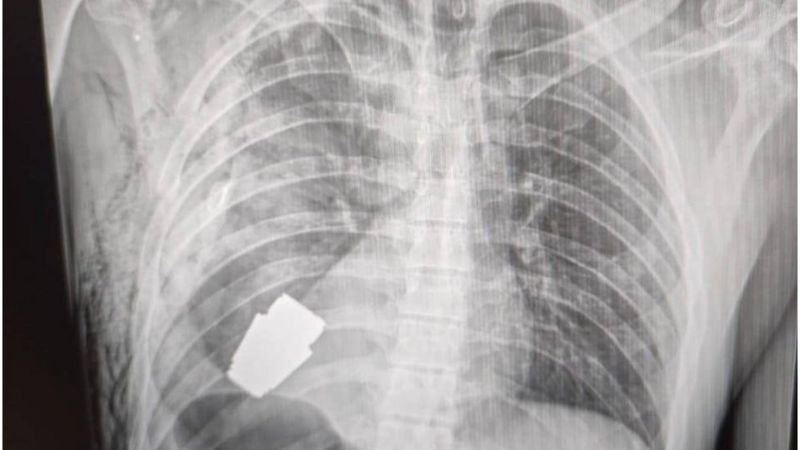

Médicos militares ucranianos realizaram com sucesso uma cirurgia delicada: retiraram uma pequena granada não detonada do fundo da cavidade torácica de um soldado ferido.

A granada de fragmentação russa VOG que estava alojada no corpo do soldado tem 4 centímetros de diâmetro e pesa 275 gramas.